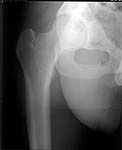

22 yrs man , semiprofessional( he earn some money from playing) basketball player got suffered in car accident.He had hip joint posterior luxation ( Pipkin 4) with little acetabular roof fragments ( nondisplaced) and anterosuperior abruption fracture of the head of the femur.

Additional injuries were severe face wounds. Emergency manipulations were reposition of the hip luxation under the radiologic control and wounds care. After reposition the CT scan was made. We found 2x3cm wide and 0.5 thick OCH fragment outside the joint surfaces , under the caput. The traction was applied.